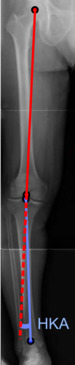

On projectional radiography, the degree of varus or valgus deformity can be quantified by the hip-knee-ankle angle,[6] which is an angle between the femoral mechanical axis and the center of the ankle joint.[7] It is normally between 1.0° and 1.5° of varus in adults.[8] Normal ranges are different in children.[9]

- Hip-knee-ankle angle by age, with 95% prediction interval.[9]